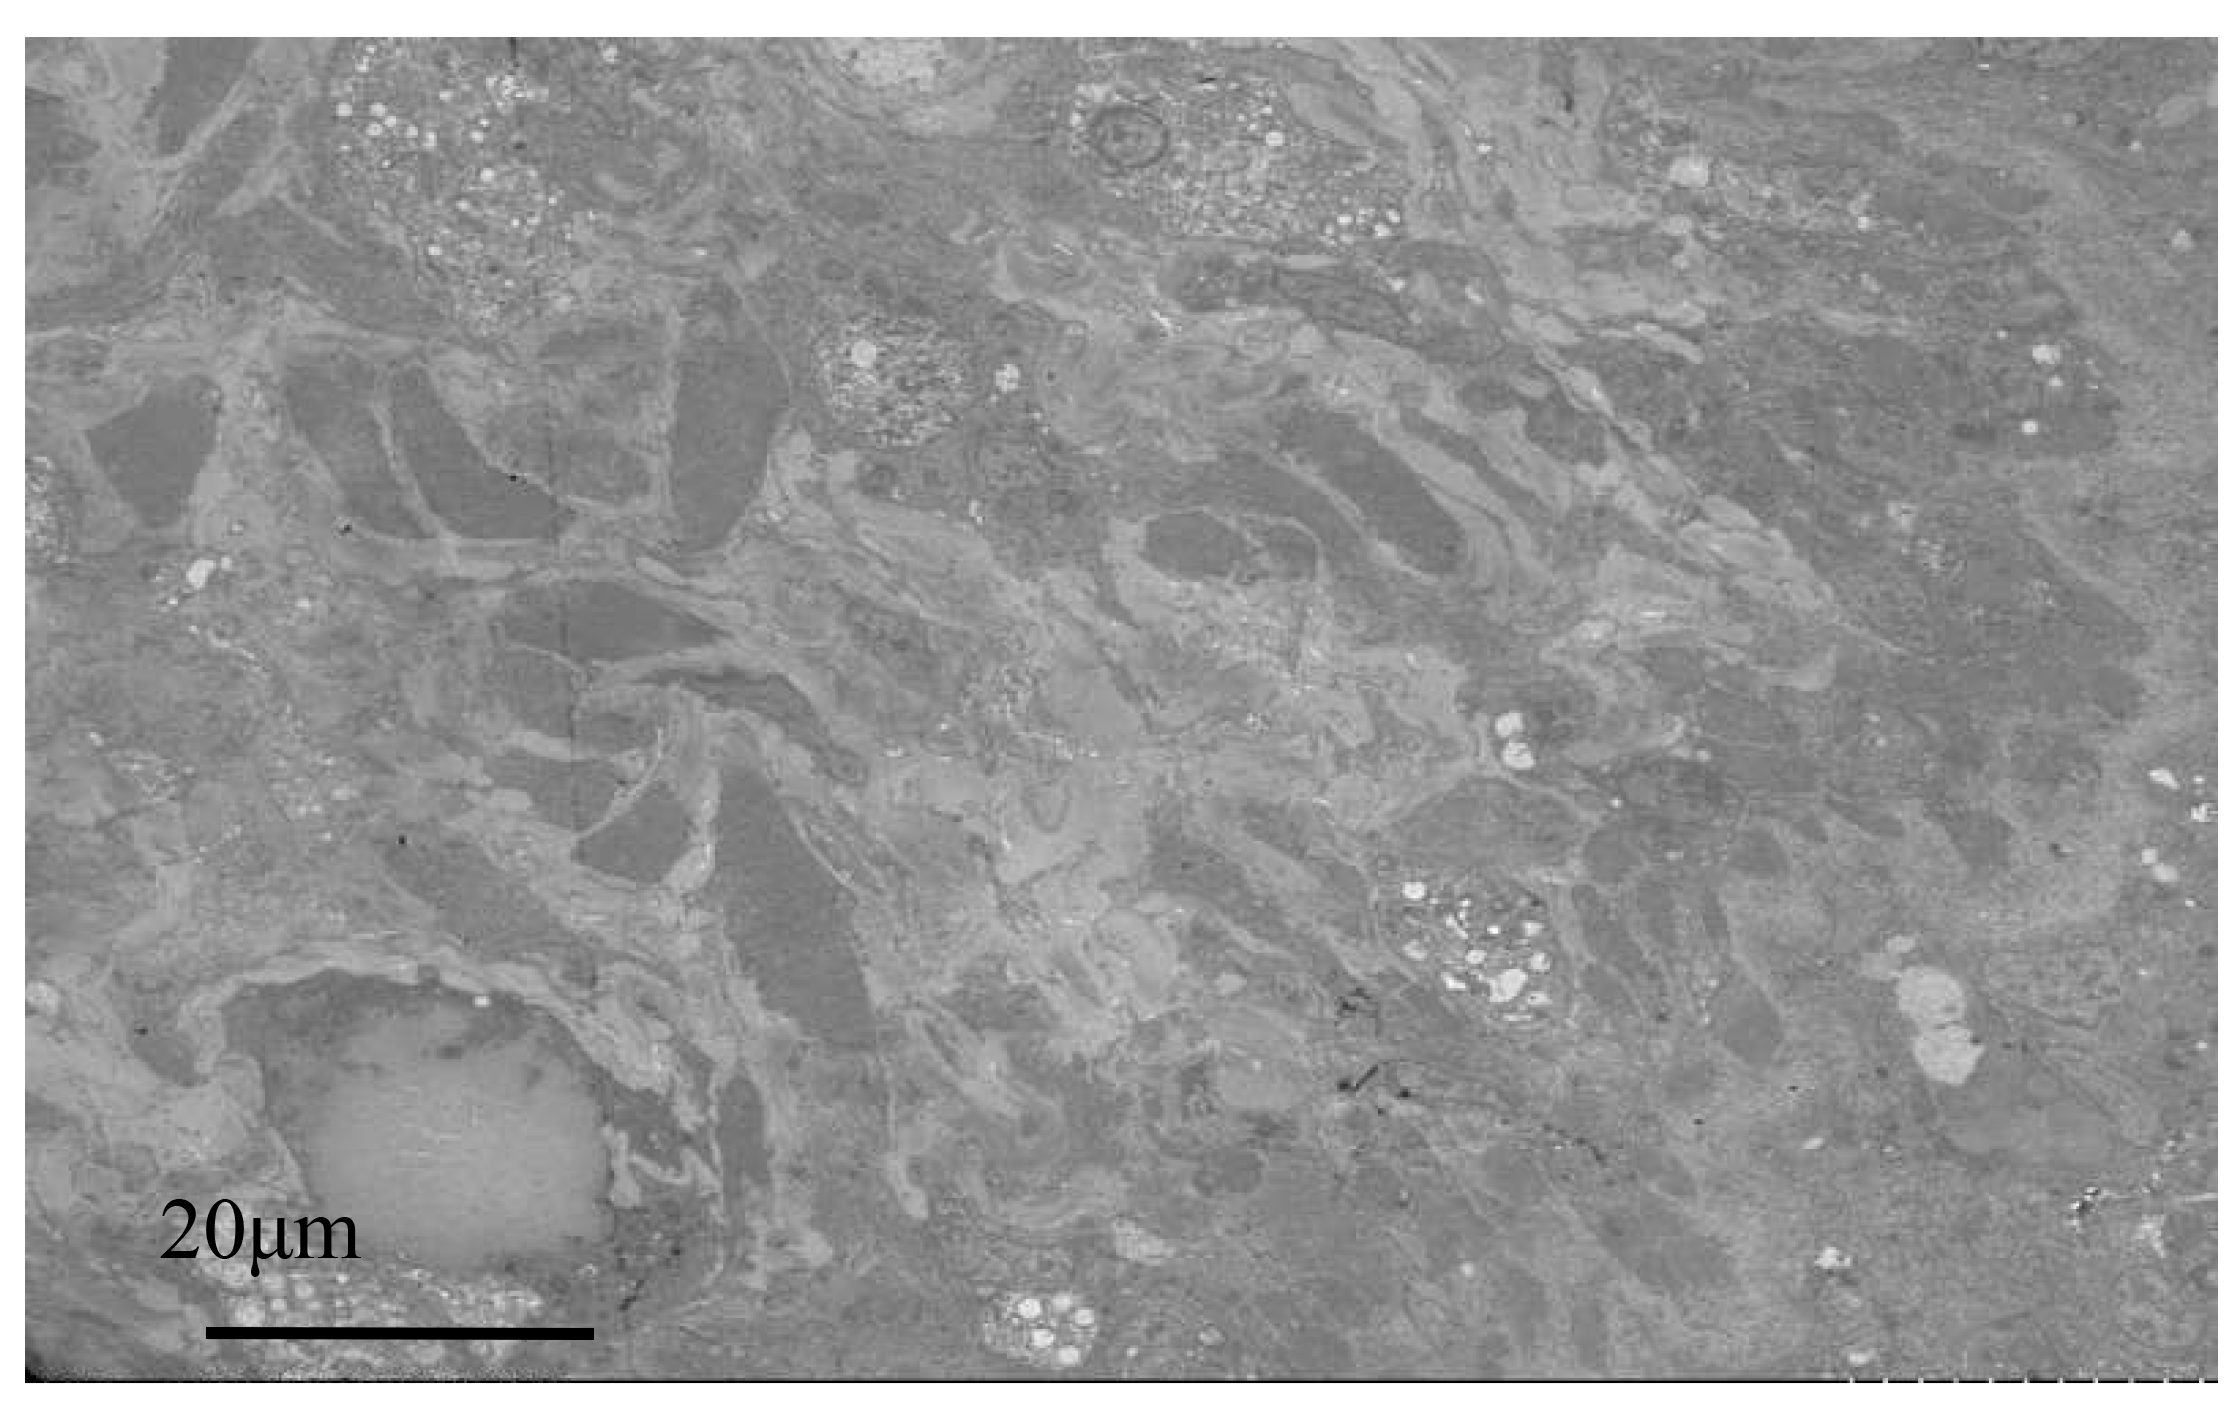

Electron microscopy images of healthy oysters showed that the epithelial layer of the mantle contained a large number of A-type columnar epidermal cells (Fig. 5A), some arranged in a monolayer and some scattered throughout the layer. The cells were about 7 to 14 μm in length, with a nucleus that occupied most of the cell. The nuclei of A-type columnar epidermal cells had relatively distinct euchromatin and heterochromatin, which were mostly located in the middle and lower parts of the cells. The organelles were relatively intact. After infection by Polydora (Fig. 5B), the overall image of the oyster mantle appeared darker than that of healthy individuals, with a particularly prominent staining of the epithelial layer area. This was due to the abnormal increase of secretion granules and pigment particles in the epithelial layer caused by the Polydora infection. The HE staining also confirmed this, as the pigment particles and secretion granules in the epithelial layer area of the marginal membrane protrusion of the infected individual were significantly increased, and the internal connective tissue area was significantly darker than that of healthy individuals.

Below the basement membrane, there was some disordered white zona pellucida (Fig. 6), consisting of electron-transparent granulocytes and secretory cells, that flooded between the epithelium and connective tissue layers. The overall structure inside the marginal membrane of healthy oysters was clear, with a normal nucleus morphology, complete nuclear membrane, and no chromatin shrinkage or vacuolization inside the nucleus. The outer mitochondrial membrane was clear, and the inner crest was relatively clear. Lysosomes were small, with a clear outer membrane and homogeneous internal substance, and the endoplasmic reticulum was laminated and relatively normal (Fig. 7A). In infected individuals, cells showed obvious pathological changes, with small fractures in the nuclear membrane, chromatin shrinkage, and vacuolization in the nucleus. A large part of lysosomes, the Golgi apparatus, endoplasmic reticulum, and mitochondria had dissolved and disappeared, and the only remaining morphological structure of the endoplasmic reticulum and cellular mitochondria was not obvious, showing semi-degenerate and dissolved forms. The cytoplasm also appeared lysed and there was severe vacuolization (Fig. 7B).